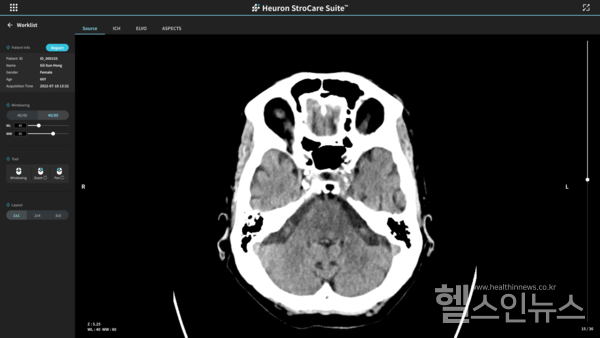

휴런 스트로케어 스위트는 비조영 CT만으로 응급 뇌 대혈관 폐색 여부를 분석하는 AI 솔루션으로 응급실에 내원한 급성 뇌졸중환자의 뇌 CT 영상을 자동 분석해 대혈관폐색 의심 환자를 선별하고 우선 판독을 위한 의료진 알람 서비스를 제공한다. 응급 뇌 대혈관 폐색 환자의 우선 순위 분류를 통해 치료 개시 시간을 단축시켜 골든타임 내 환자를 빠르게 치료하는 데 도움이 돼 뇌졸중 환자 예후 개선을 기대할 수 있다는 회사측의 설명이다.